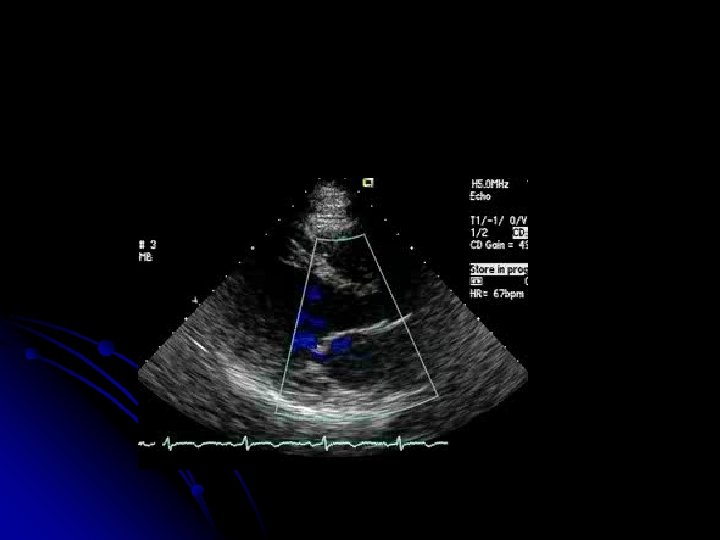

The Diagnostic testing used to evaluate the presence & severity of Mitral Stenosis includes: ECG Chest Radiograph 2 D Echocardiogram Doppler Study Trans. Esophageal Echocardiography

LEFT PARASTERNAL, LONG AXIS VIEW STENOTIC MITRAL VALVE